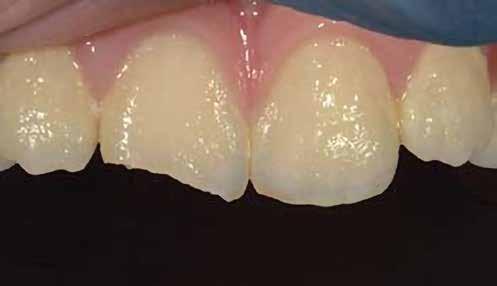

A betétek készítéséről készülök előadást tartani. Ez a terület hallgató korom óta tetszett, és mára a rendelőnkben végzett kezelések jelentős részét teszi ki.Héjkerámiák ragasztására váró fogak.

A cikkünkben bemutatásra kerülő eset ellátása során preparációt héjak készre vitele során a platinafólia technikát alkalmaztuk.

A fogászati kezelések során manapság már nem kizárólag az esztétikai megjelenés helyreállítására törekszünk. Sokszor a kedvezőtlen esztétikai megjelenés hátterében álló okok következményes módon a fogazat funkcionális működését is károsítják, így a kezelések során ezeknek a helyreállításával is foglalkoznunk kell. A különböző funkcionális és esztétikai diszkrepanciák kezelésére számtalan módszer létezik, ám ezen fogászati beavatkozások mindegyikében közös, hogy a kivitelezésük során nagyon szoros együttműködésre van szükség a kezelést végző fogorvos és a munkáját segítő fogtechnikus között. Az alábbi esetbemutatás során egy fiatal hölgypáciens fogazatának héjak alkalmazásával történő esztétikai és funkcionális rehabilitációját szeretnénk ismertetni.

A páciens fogazata esztétikai megjelenésének és funkcionális működésének a lehető legtöbb, saját foganyag megtartása mellett történő helyreállítása (1. és 3. ábra).